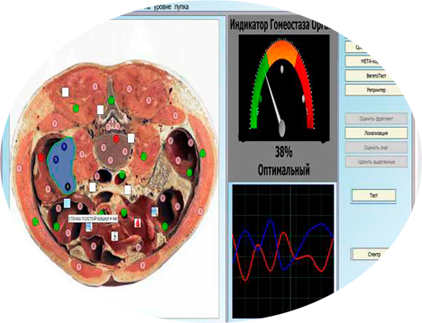

Preventive health care must be planned and executed ahead of time, even when illness is absent."Our scanning techniques provide in-depth know how of the functioning of all the vital human organs and helps in predicting and identify the illness beforehand or during its existence there by giving right direction to the treatment of the patient for the restoration of health to perfection." Unique combinations of treatment to revitaiize the autonomics nervous system nof the body by stimulating flow of vital energy in spine and eliminating all toxins of the body. Quantum Magnetic Resonance Body Analyzer Multilingual Sub Health USA (With CE Standard) The Quantum Health Analyzer Have 41 Reports